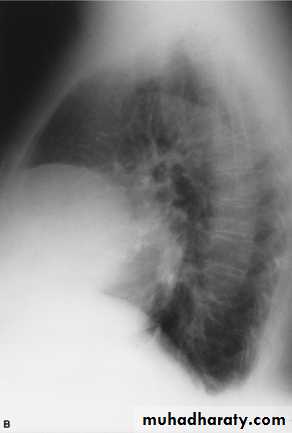

Pleural Effusion on Chest Radiographs.

Posteroanterior (A) and lateral (B) chest radiographs demonstrate the typical meniscoid appearance (arrows) in a patient with a left pleural effusion